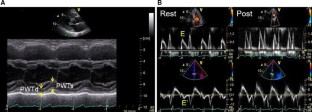

Fifty-eight elderly patients (age = 74 ± 6 years) who underwent treadmill stress echocardiography were studied. All patients had normal LV wall motion at rest, and patients with exercise-induced wall motion abnormality were excluded. The DWS was calculated as follows: DWS = (PWTs − PWTd)/PWTs, where PWTs is the LV posterior wall thickness at end-systole and PWTd is that at end-diastole. As previously reported, DWS ≤ 0.33 was defined as low DWS and E/E′ ≥15.0 was defined as a marker of increased LV filling pressure.

Fig. 1